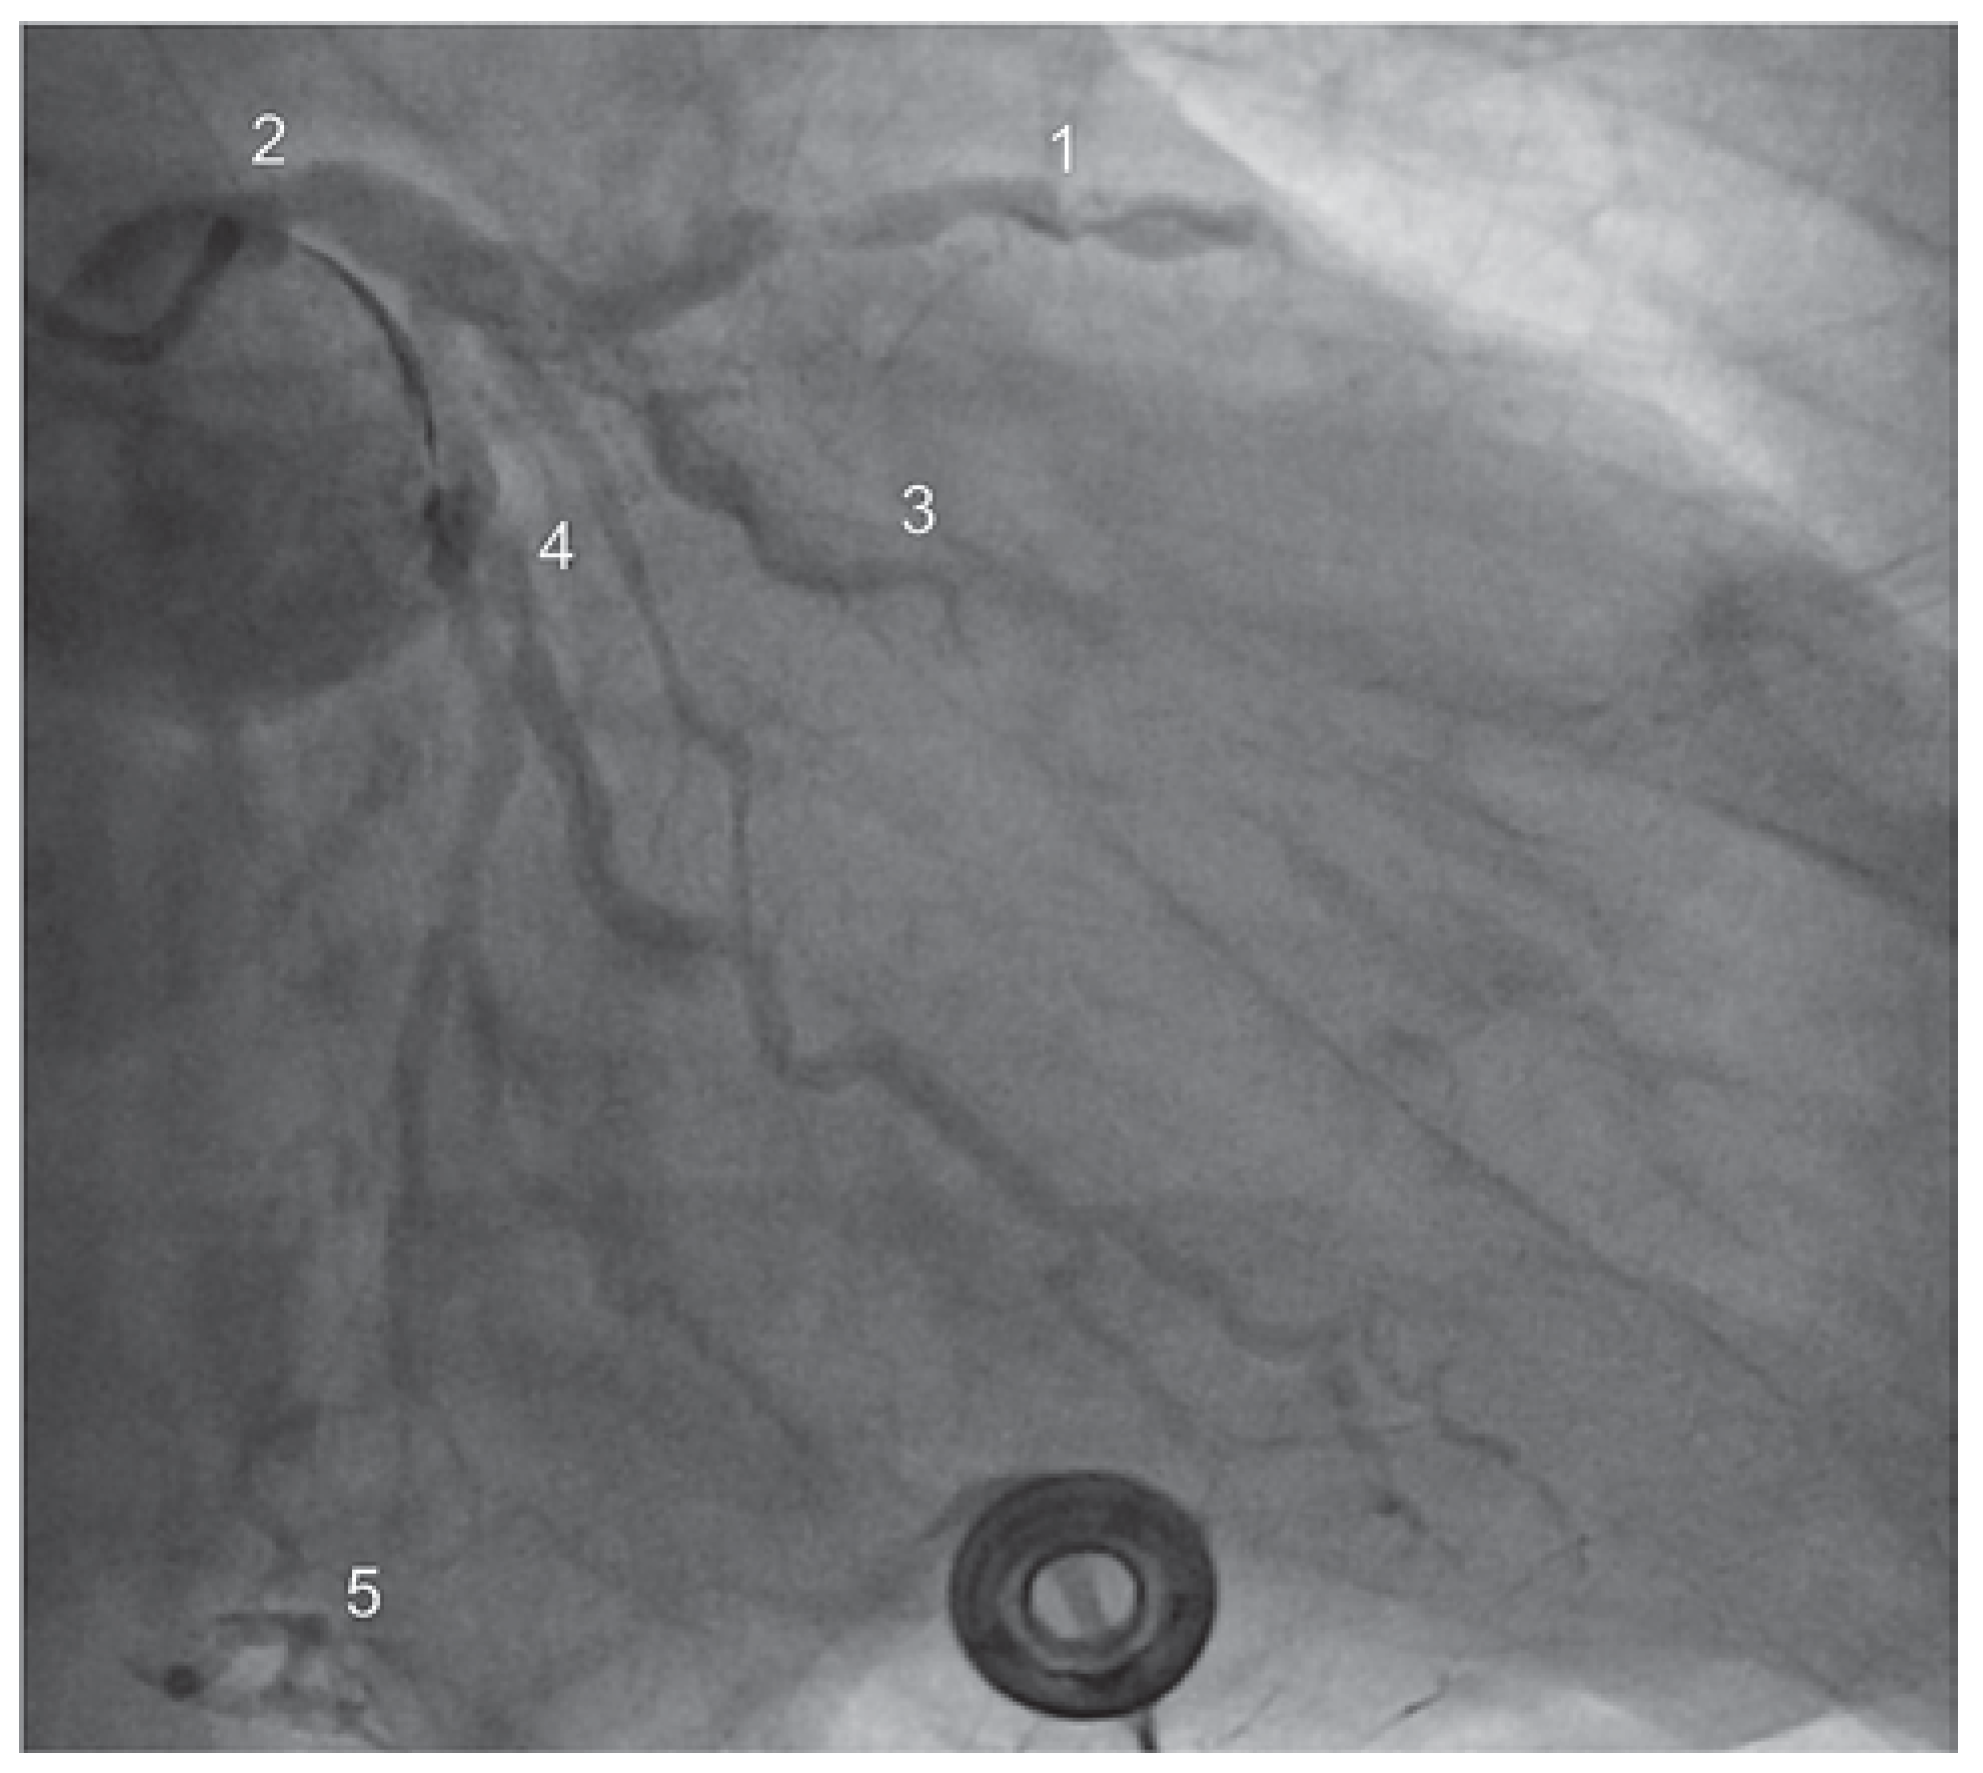

Die Zuweisung des 75-jährigen Patienten erfolgte durch ein Regionalspital mit dem Bild eines subakutem Nicht-ST-Hebungsinfarktes und beginnendem kardiogenem Schock (Killip Klasse III-VI). Die Labordiagnostik zeigte erhöhte Herzenzyme (hochsensitives Troponin 0,7). Die Koronarangiographie ergab eine schwere koronare 2-Gefäss-Erkrankung mit Hauptstammbeteiligung (90% Stenose des distalen Hauptstamms sowie Verschluss des proximalen RCX und 70% Stenose des proximalen RIVA) (Abbildung 3). Bei kleiner rechter Koronararterie liess sich zudem ein Linksversorgertyp identifizieren.

Abbildung 3. Koronarangiographie vor Intervention – Fall 2. 1 – RIVA, 2 – Hauptstamm, 3 – RCX.

Aufgrund der Koronaranatomie bestand eine Hochrisiko-Konstellation für die indizierte perkutane Koronarintervention (PCI). Es erfolgte der interdisziplinäre Entscheid zur Einlage einer veno-arteriellen ECMO, die wie beim oben beschriebenen Patienten im-plantiert wurde. Nach komplikationsloser Einlage erfolgte die extrakorporale Zirkulation mit schliesslich 2 l/min, worunter sich eine stabile Hämodynamik zeigte. Unter dieser ECMO-Unterstützung gelang mittels PTCA und anschliessendem V-Stenting eine Revaskularisation der Hauptstammstenose sowie der proximalen RIVAund RCX-Stenosen (Abbildung 4). Bei stabiler postinterventioneller Hämodynamik erfolgte die Entfernung der ECMO noch in gleicher Sitzung.

Abbildung 4. Koronarangiographie nach Intervention – Fall 2.